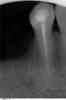

andrez Опубликовано 4 февраля, 2011 Поделиться Опубликовано 4 февраля, 2011 Здравствуйте !Следующая проблема с зубами:Время от времени(особенно когда застужу) возникает несильная, но постоянно ноющая боль в зубах. Практически все зубы депульпированы.Это продолжается от нескольких дней до нескольких недель(время от времени затухая) причем в разных местах от левой четвертки(рядом с временной одиночной коронкой на панорамном снимке) до правой тройки вверху и от левой четвертки до правой четверки внизу.После панорамного снимка, удалил нерв в левой семерке(снимок 7l) и в правой четверке (снимок 4r), а также переделал правую семерку(7r)(все - нижняя челюсть). Улучшение не случилось.Стоматолог посоветовал обратится к неврологу, что я и собираюсь сделать в ближайшее время, но хочется быть уверенным, что со стороны стоматологии все сделано.Еще один вопрос по нижней правой семерке: на панорамном снимке показывается, что один канал не запломбирован(этот зуб делал очень давно и он не беспокоил). При попытке его переделать, до конца пройти не удалось(снимок 7r). Врач сказала, что скорее всего его пломбировали "не контрастным материалом", который раньше применялся. Теперь вопрос: надо ли его пытаться еще раз перепломбировать у другого врача( я собираюсь на него мост крепить).Спасибо.Андрей З.Москва Ссылка на комментарий

andrez Опубликовано 8 февраля, 2011 Автор Поделиться Опубликовано 8 февраля, 2011 Подскажите, пожалуйста по 44 и 47 зубам(два нижних снимка). Надо их перелечивать? Ссылка на комментарий